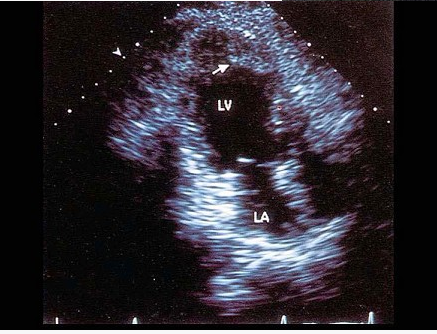

哪个是该病例最可能的诊断()。

A、真性室壁瘤

B、假性室壁瘤

C、室壁憩室

D、扩张型心肌病

E、膜部瘤

真性室壁瘤(室壁瘤)与假性室壁瘤的主要区别在于()。

A、室壁局部有膨出

B、室壁运动呈矛盾运动

C、室壁变薄

D、瘤壁与室壁是否有连续性

E、真性室壁瘤的内层为心内膜,而假性室壁瘤为心肌组织或心包